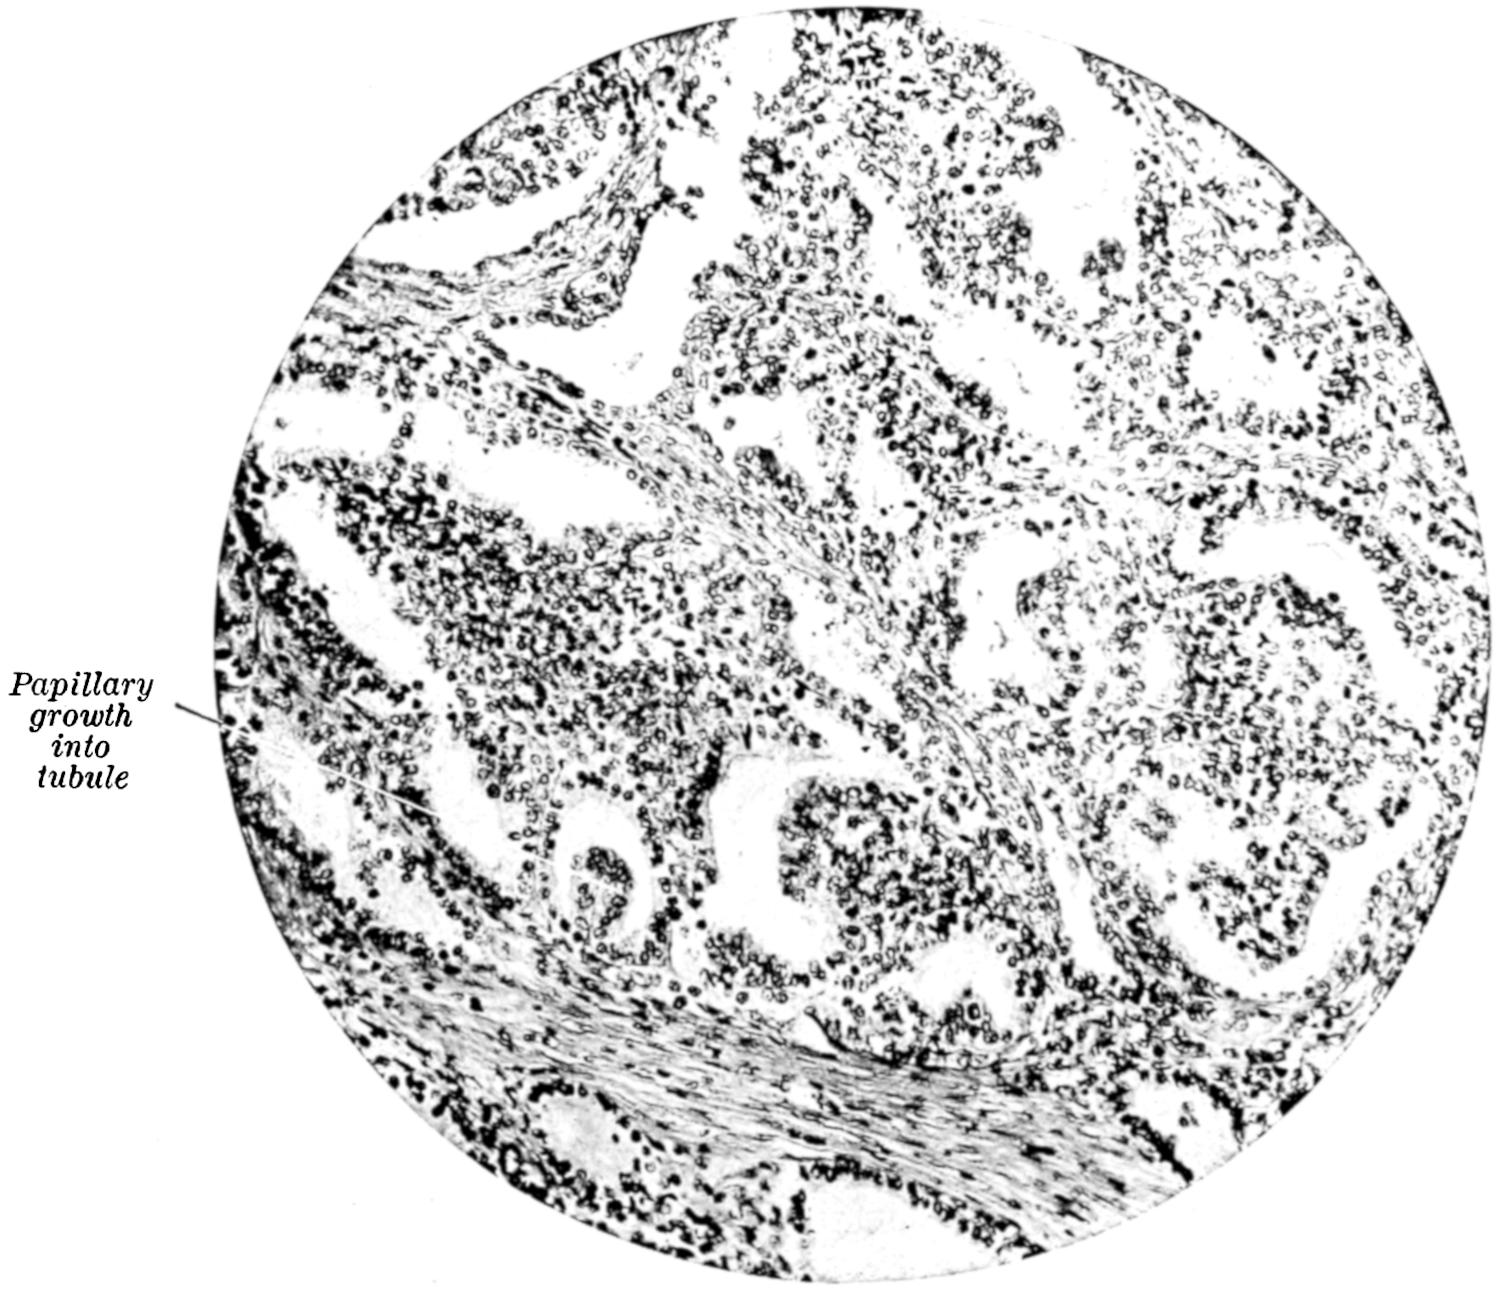

PLATE I

Fig. I.

Fig. II.

Fig. III.

Fig. IV.

Fig. V.

Fig. VI.

Fig. VII.

Fig. VIII.

DRAWN BY J. N. Z. CHASE

PLATE I.

BLOOD.

(Ehrlich triple stain.)

(Prepared by Dr. I. P. Lyon.)

Fig. I. TYPES OF LEUCOCYTES.

a. Polymorphonuclear Neutrophile. b. Polymorphonuclear Eosinophile. c. Myelocyte (Neutrophilic). d. Eosinophilic Myelocyte. e. Large Lymphocyte (large Mononuclear). f. Small Lymphocyte (small Mononuclear).

Fig. II. NORMAL BLOOD.

Field contains one neutrophile. Reds are normal.

Fig. III. ANÆMIA, POST-OPERATIVE (secondary).

The reds are fewer than normal, and are deficient in hæmoglobin and somewhat irregular in form. One normoblast is seen in the field, and two neutrophiles and one small lymphocyte, showing a marked post-hæmorrhagic anæmia, with leucocytosis.

Fig. IV. LEUCOCYTOSIS, INFLAMMATORY.

The reds are normal. A marked leucocytosis is shown, with five neutrophiles and one small lymphocyte. This illustration may also serve the purpose of showing the leucocytosis of malignant tumor.

Fig. V. TRICHINOSIS.

A marked leucocytosis is shown, consisting of an eosinophilia.

Fig. VI. LYMPHATIC LEUKÆMIA.

Slight anæmia. A large relative and absolute increase of the lymphocytes (chiefly the small lymphocytes) is shown.

Fig. VII. SPLENO-MYELOGENOUS LEUKÆMIA.

The reds show a secondary anæmia. Two normoblasts are shown. The leucocytosis is massive. Twenty leucocytes are shown, consisting of nine neutrophiles, seven myelocytes, two small lymphocytes, one eosinophile (polymorphonuclear) and one eosinophilic myelocyte. Note the polymorphous condition of the leucocytes, i. e., their variations from the typical in size and form.

Fig. VIII. VARIETIES OF RED CORPUSCLES.

a. Normal Red Corpuscle (normocyte). b, c. Anæmic Red Corpuscles. d-g. Poikilocytes. h. Microcyte. i. Megalocyte. j-n. Nucleated Red Corpuscles. j, k. Normoblasts. l. Microblast. m, n. Megaloblasts.

The value of a careful blood examination is well illustrated by Plate I, prepared by Dr. Irving P. Lyon, in which are displayed the alterations of greatest interest to the surgeon.